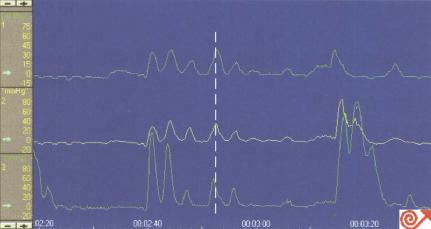

2 嘱患者做数次(如:10次)湿咽,检测吞咽后的LES松驰(图8.31)。因检测过程中患者常取平卧位,可用10~50ml注射器装满室温水,每次向患者口腔内注入温水5~10ml,之后嘱患者吞咽进行检测。检测过程中两次湿咽间应停顿至少20~30秒,并于每次湿咽时在计算机屏幕上做好标记。

吞咽时LES松弛

图8.31吞咽时LES松弛。游标指示咽部收缩时LES即开

始松弛,白色水平线表示LES松弛持续时间。

(a)如吞咽时LES完全松驰,则压力降至接近胃内压基线水平

(b)LES完全性松驰的定义为:松驰率大于90%(残余压低于5mmHg)